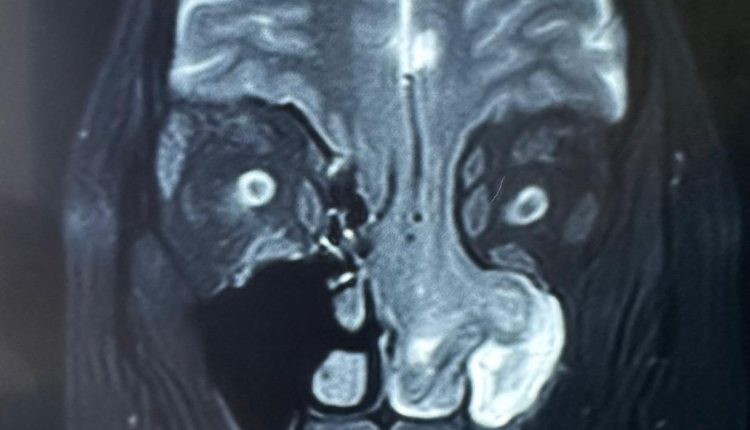

Dr. Ashish Vashishth, HOD & Consultant – ENT (Otorhinolaryngology, Head and Neck and Cranial Base Surgery, Ear, Nose and Throat) said, “When the patient came to us with persistent nasal obstruction, an initial endoscopic examination in our ENT department raised suspicion of a rare condition. Targeted CT and MRI scans revealed that part of her brain had herniated through the eroded skull base into the nasal cavity. This case certainly highlights the importance of a thorough diagnostic pathway and consulting the right specialists at the right time. What made this case challenging was the technical precision needed to manage such a delicate and high-risk cranial base reconstruction. The success of this case truly highlights the strength of a multidisciplinary and diagnostic-first approach.”

Dr. Anurag Saxena, Cluster Head-Delhi NCR, Neurosurgery, said, “This was an extremely rare and technically demanding case. The patient was at significant risk of developing a life-threatening stroke, as the brain’s blood vessels were also herniating down along with the brain tissue. Even the slightest injury to these vessels could have caused devastating complications. Almost half of the frontal and basal parts of the brain were hanging down through the skull base defect, which made performing the surgery exceptionally complex. Through a carefully coordinated endoscopic and transcranial approach, we successfully repositioned the brain, reconstructed the skull base, and ensured her safe recovery. The patient has now recovered well and is leading a normal life under regular follow-up care.”